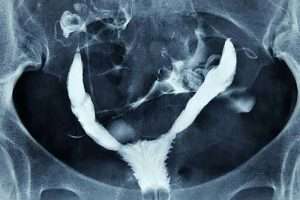

“T” Şeklinde Rahim

Bölmeli Rahim